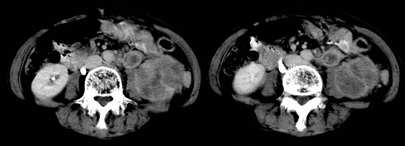

左肾不规则软组织肿块,内见低密度坏死区,与正常肾实质分界不清,左肾明显增大,增强呈不规则条索状强化,肾盂及左输尿管上段扩张。肾周脂肪层受侵、模糊。印象:典型左肾癌。

平扫,表现为肾实质肿块,呈分叶状,肿块密度不均,内有不规则低密度区(陈旧性出血?坏死?)有的似呈囊性,增强明显不均一强化,与肾实质相比呈相对低密度的不均一肿块,肾周脂肪间隙可见,肾前筋膜未见增后,肾血管及腹主动脉旁未见肿大淋巴结影

左侧肾癌并肾静脉癌栓.腹膜后淋巴结肿大转移.

左肾癌累及左输尿管,左肾静脉无受累征象。